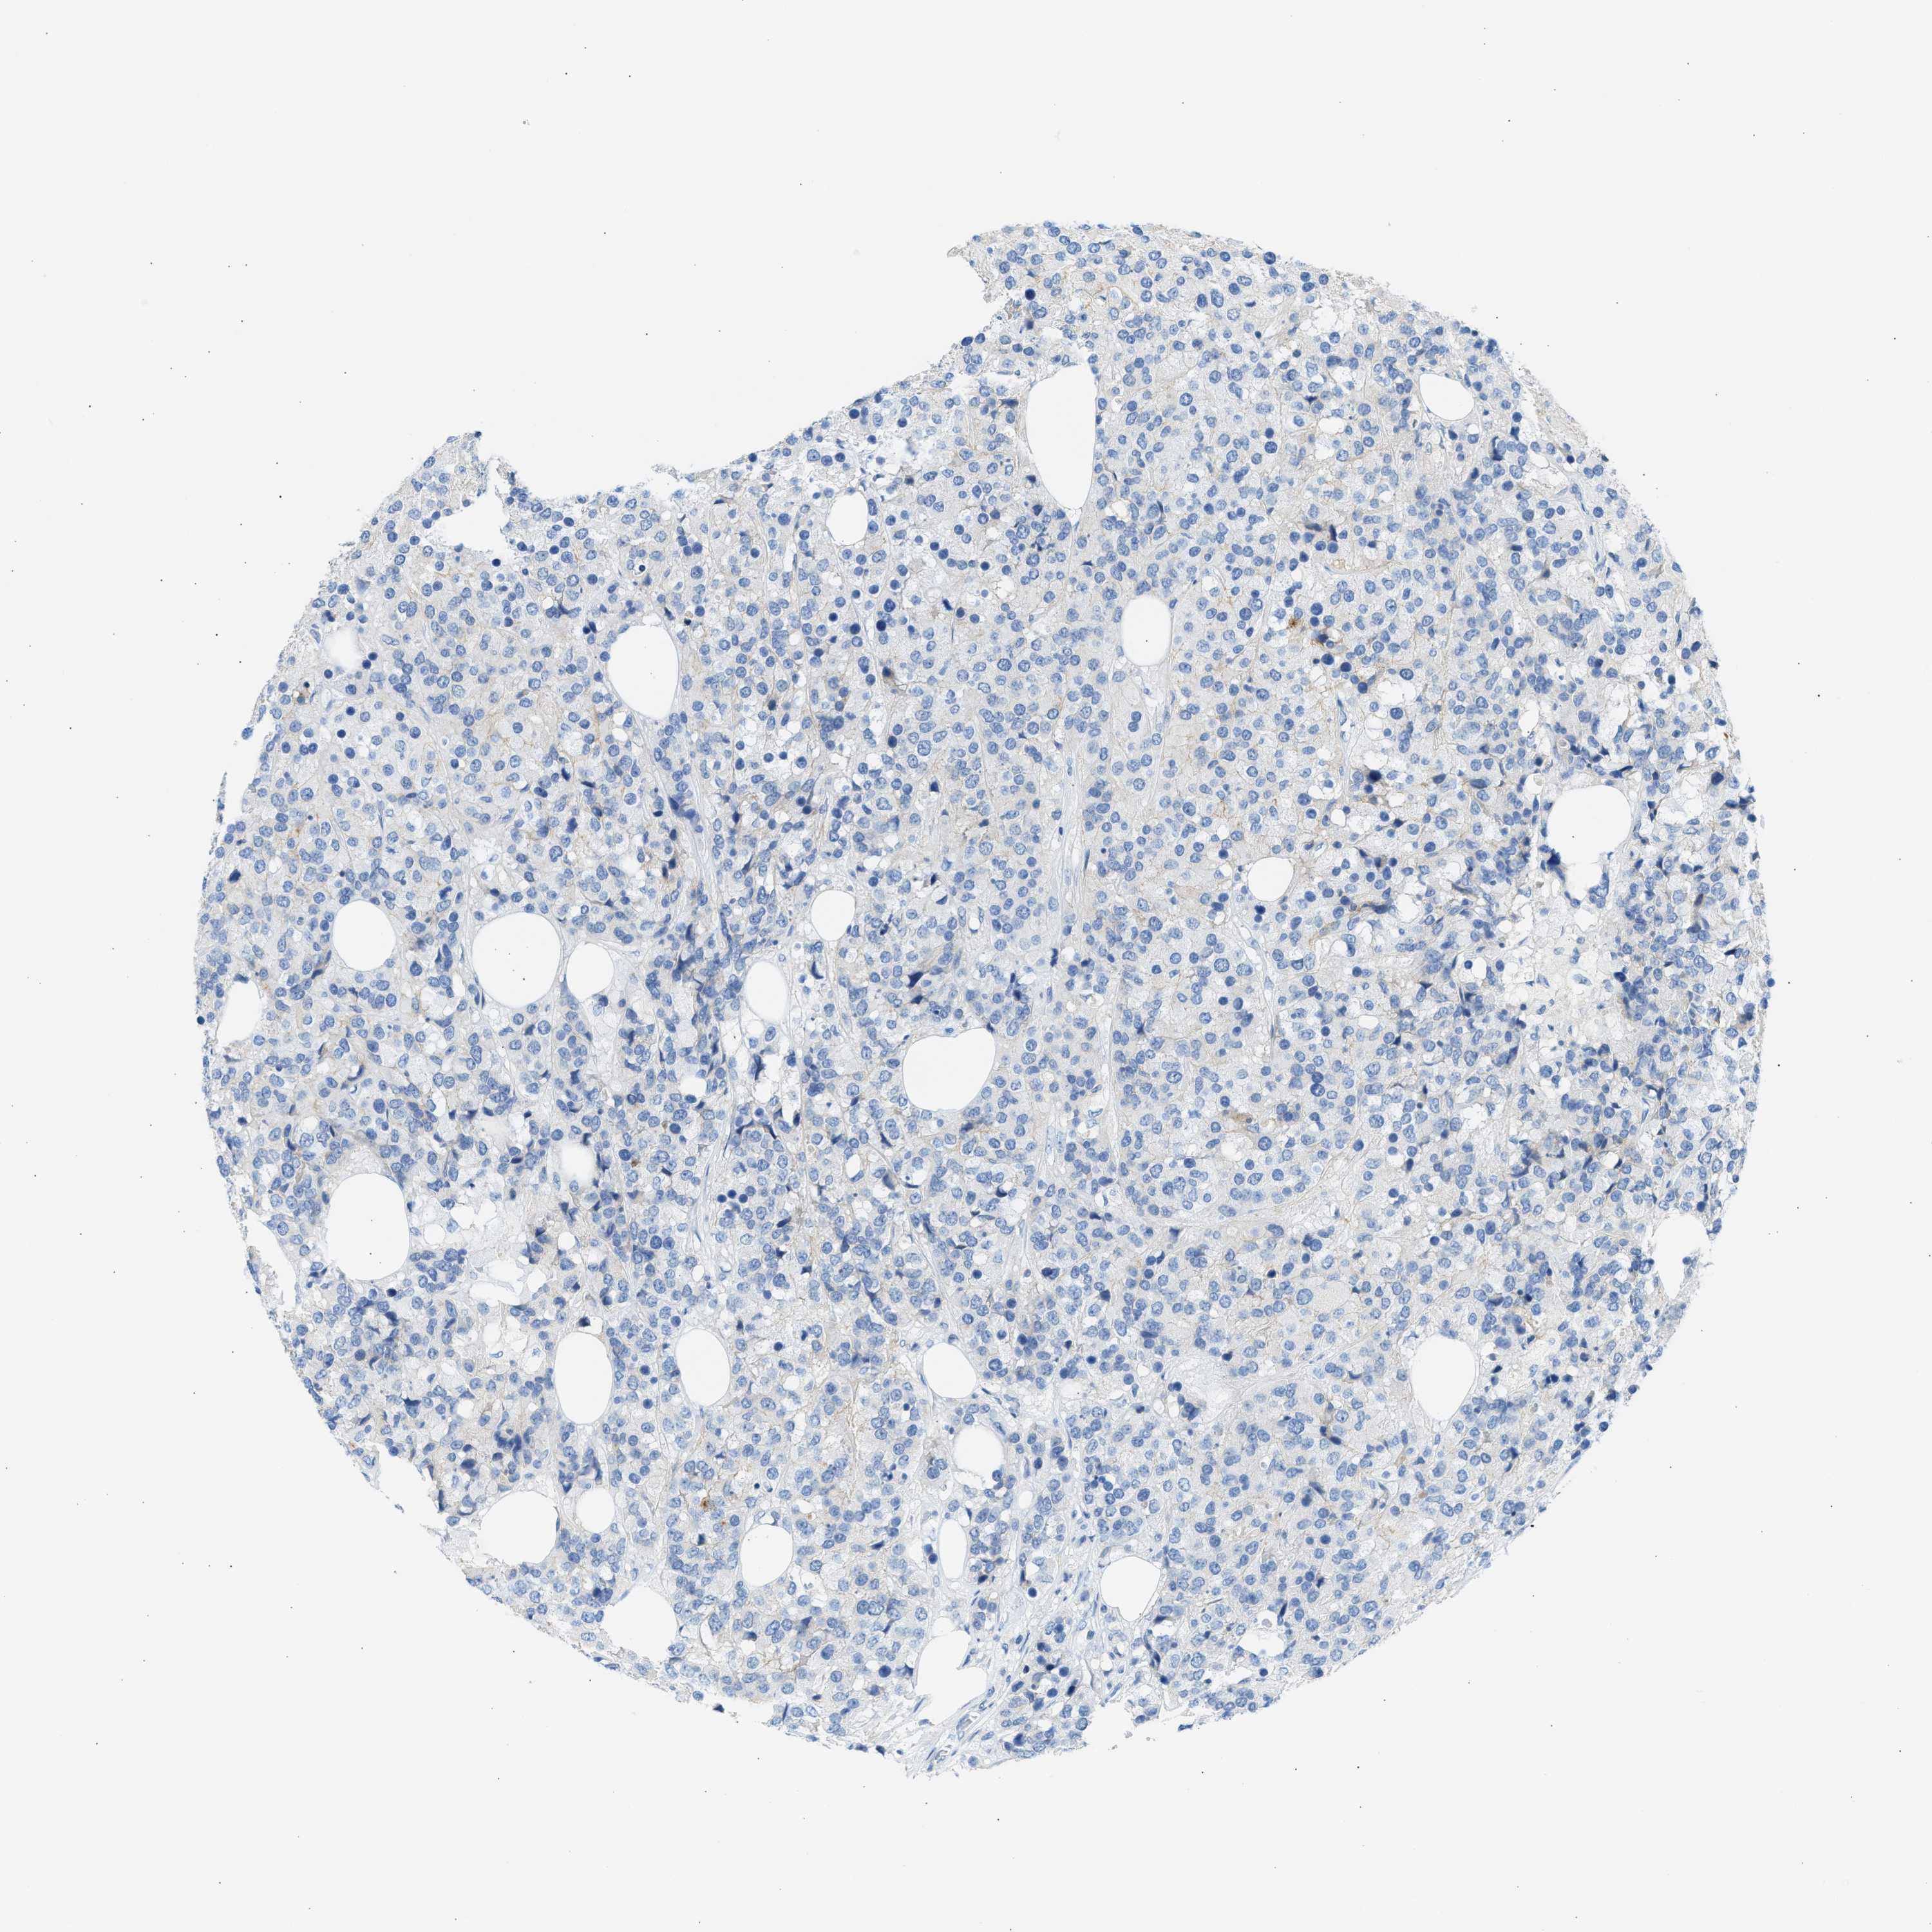

CANCER BREAST CANCER Show tissue menu

BRCA TCGA BRCA VALIDATION PROTEIN EXPRESSION

ANTIBODIES

AND

VALIDATION